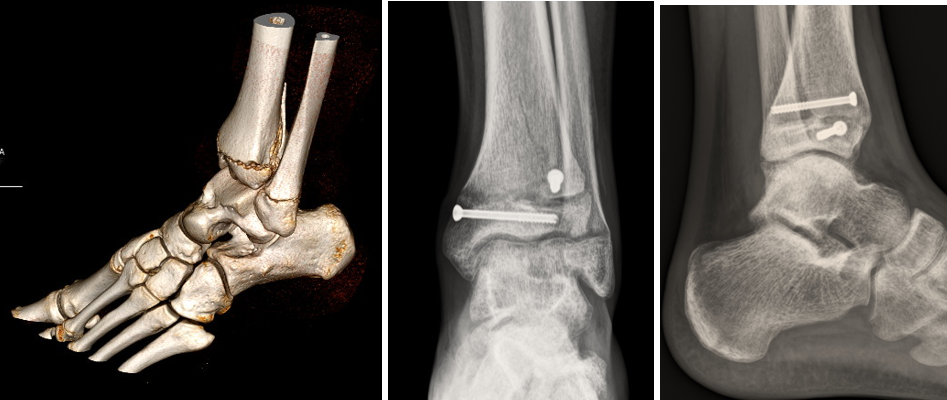

La seconda, la frattura triplana, fu originariamente descritta da descritta da Marmor nel 1970. Il suo nome è dovuto ai 3 piani dello spazio nei quali si propaga: il piano sagittale, trasverso e coronale (figura 2)

Figura 2

Si tratta quindi di una combinazione di una lesione di Salter Harris tipo II a livello della metafisi tibiale (piano coronale - proiezione laterale) e di una lesione di Salter Harris tipo III a livello dell’epifisi (piano assiale - proiezione antero posteriore).

Soventemente è costituita da 3 frammenti se l’età è inferiore ai 10 anni e da 2 frammenti se l’età è maggiore di 10 anni.

La tomografia assiale computerizzata è la metodica di scelta per studiare questo tipo di fratture e permette anche di ottenere diagnosi differenziale con la frattura di Tillaux, che riguarda solo l’epifisi, e per un adeguato planning chirurgico (fig.3,4, 5, 6 e 7).

Il trattamento di scelta per le fratture scomposta è la riduzione anatomica e la sintesi, per via percutanea o cielo aperta, con viti cannulate.

Figure 3 & 4

Figura 5, 6 & 7